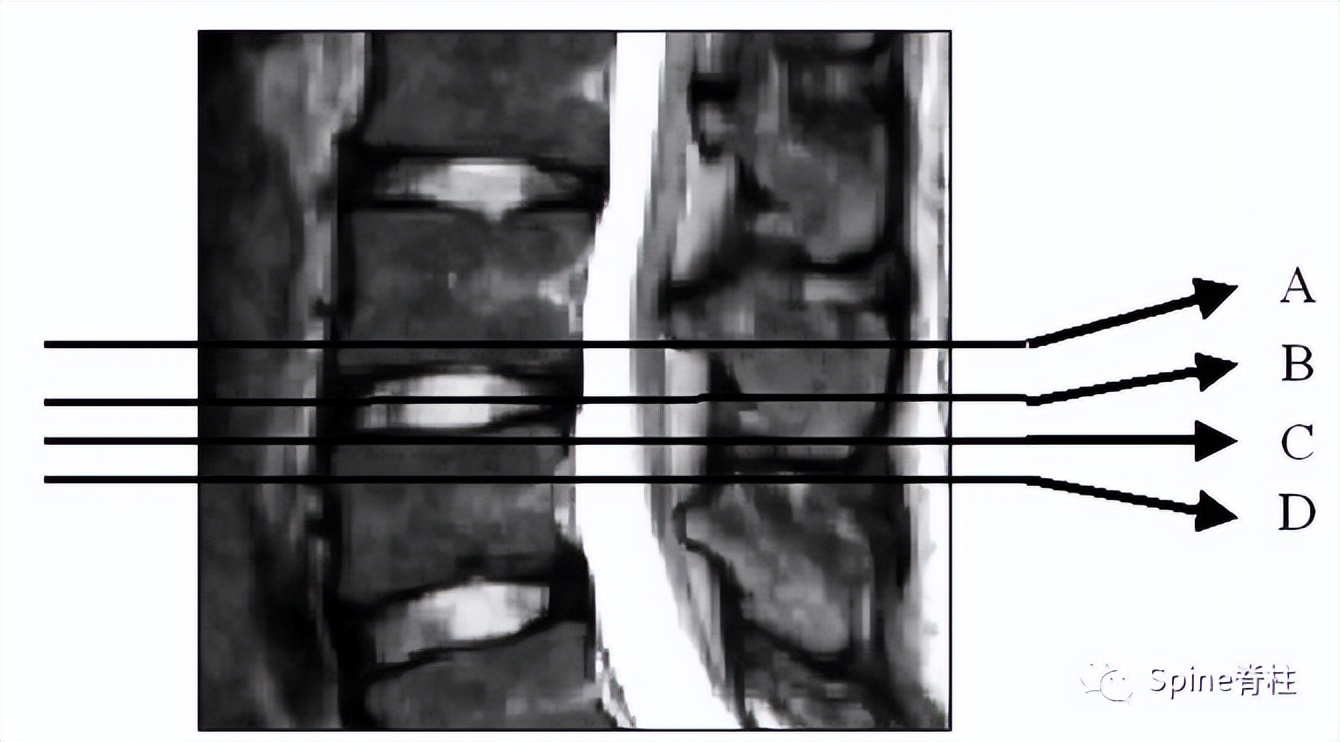

因此,Sairyo教授也提出,对于青少年腰痛患者行MRI检查时,在传统椎间盘层面的基础上(A-C线), 多加一个经椎弓根层面(D线) 。因为,A-C线椎间盘层面可很好看出青少年腰椎间盘突出和腰椎椎体后缘离断症,而D线经椎弓根层面可以早期诊断出腰椎峡部裂和腰椎椎弓根损伤。